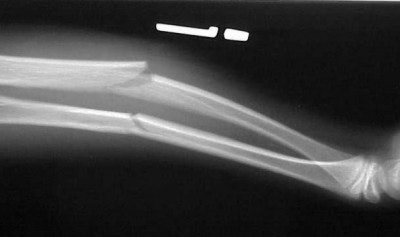

In figure 3 there is an obvious midshaft fracture of the forearm on the AP view. The film was shot with the forearm in a position of comfort on the child’s lap. On the attempted lateral, figure 4, we see that because of the deformity, it is not a true lateral. It, again, was shot cross-table with the film braced between the child and his forearm.